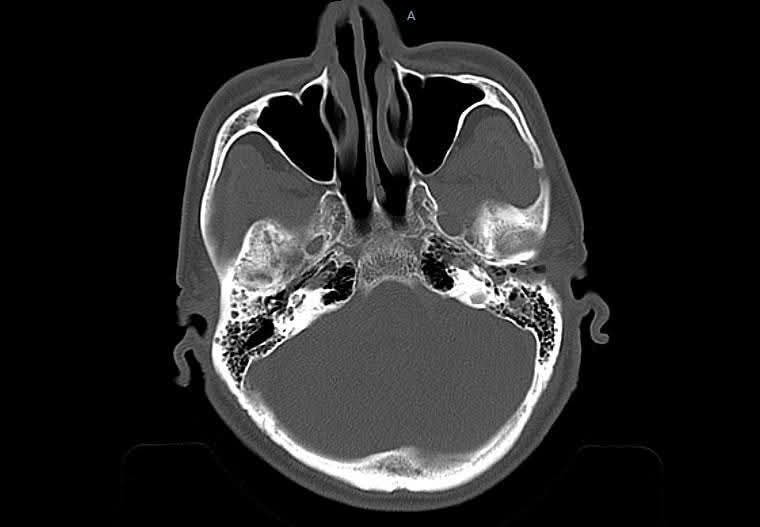

Hình ảnh tổn thương trên phim chụp - Ảnh BVCC

CT sọ não cấp cứu ghi nhận: Tụ máu dưới màng cứng hai bán cầu, bên trái dày tới 18 mm; Xuất huyết dưới nhện rải rác hai bán cầu; Đường giữa lệch 15 mm – dấu hiệu chèn ép não nghiêm trọng; Vỡ xương thái dương phải, xương đá trái, kèm tụ dịch sào bào chũm.

Chẩn đoán xác định: Chấn thương sọ não nặng; Tụ máu dưới màng cứng hai bán cầu; Xuất huyết dưới nhện; Vỡ xương sọ.